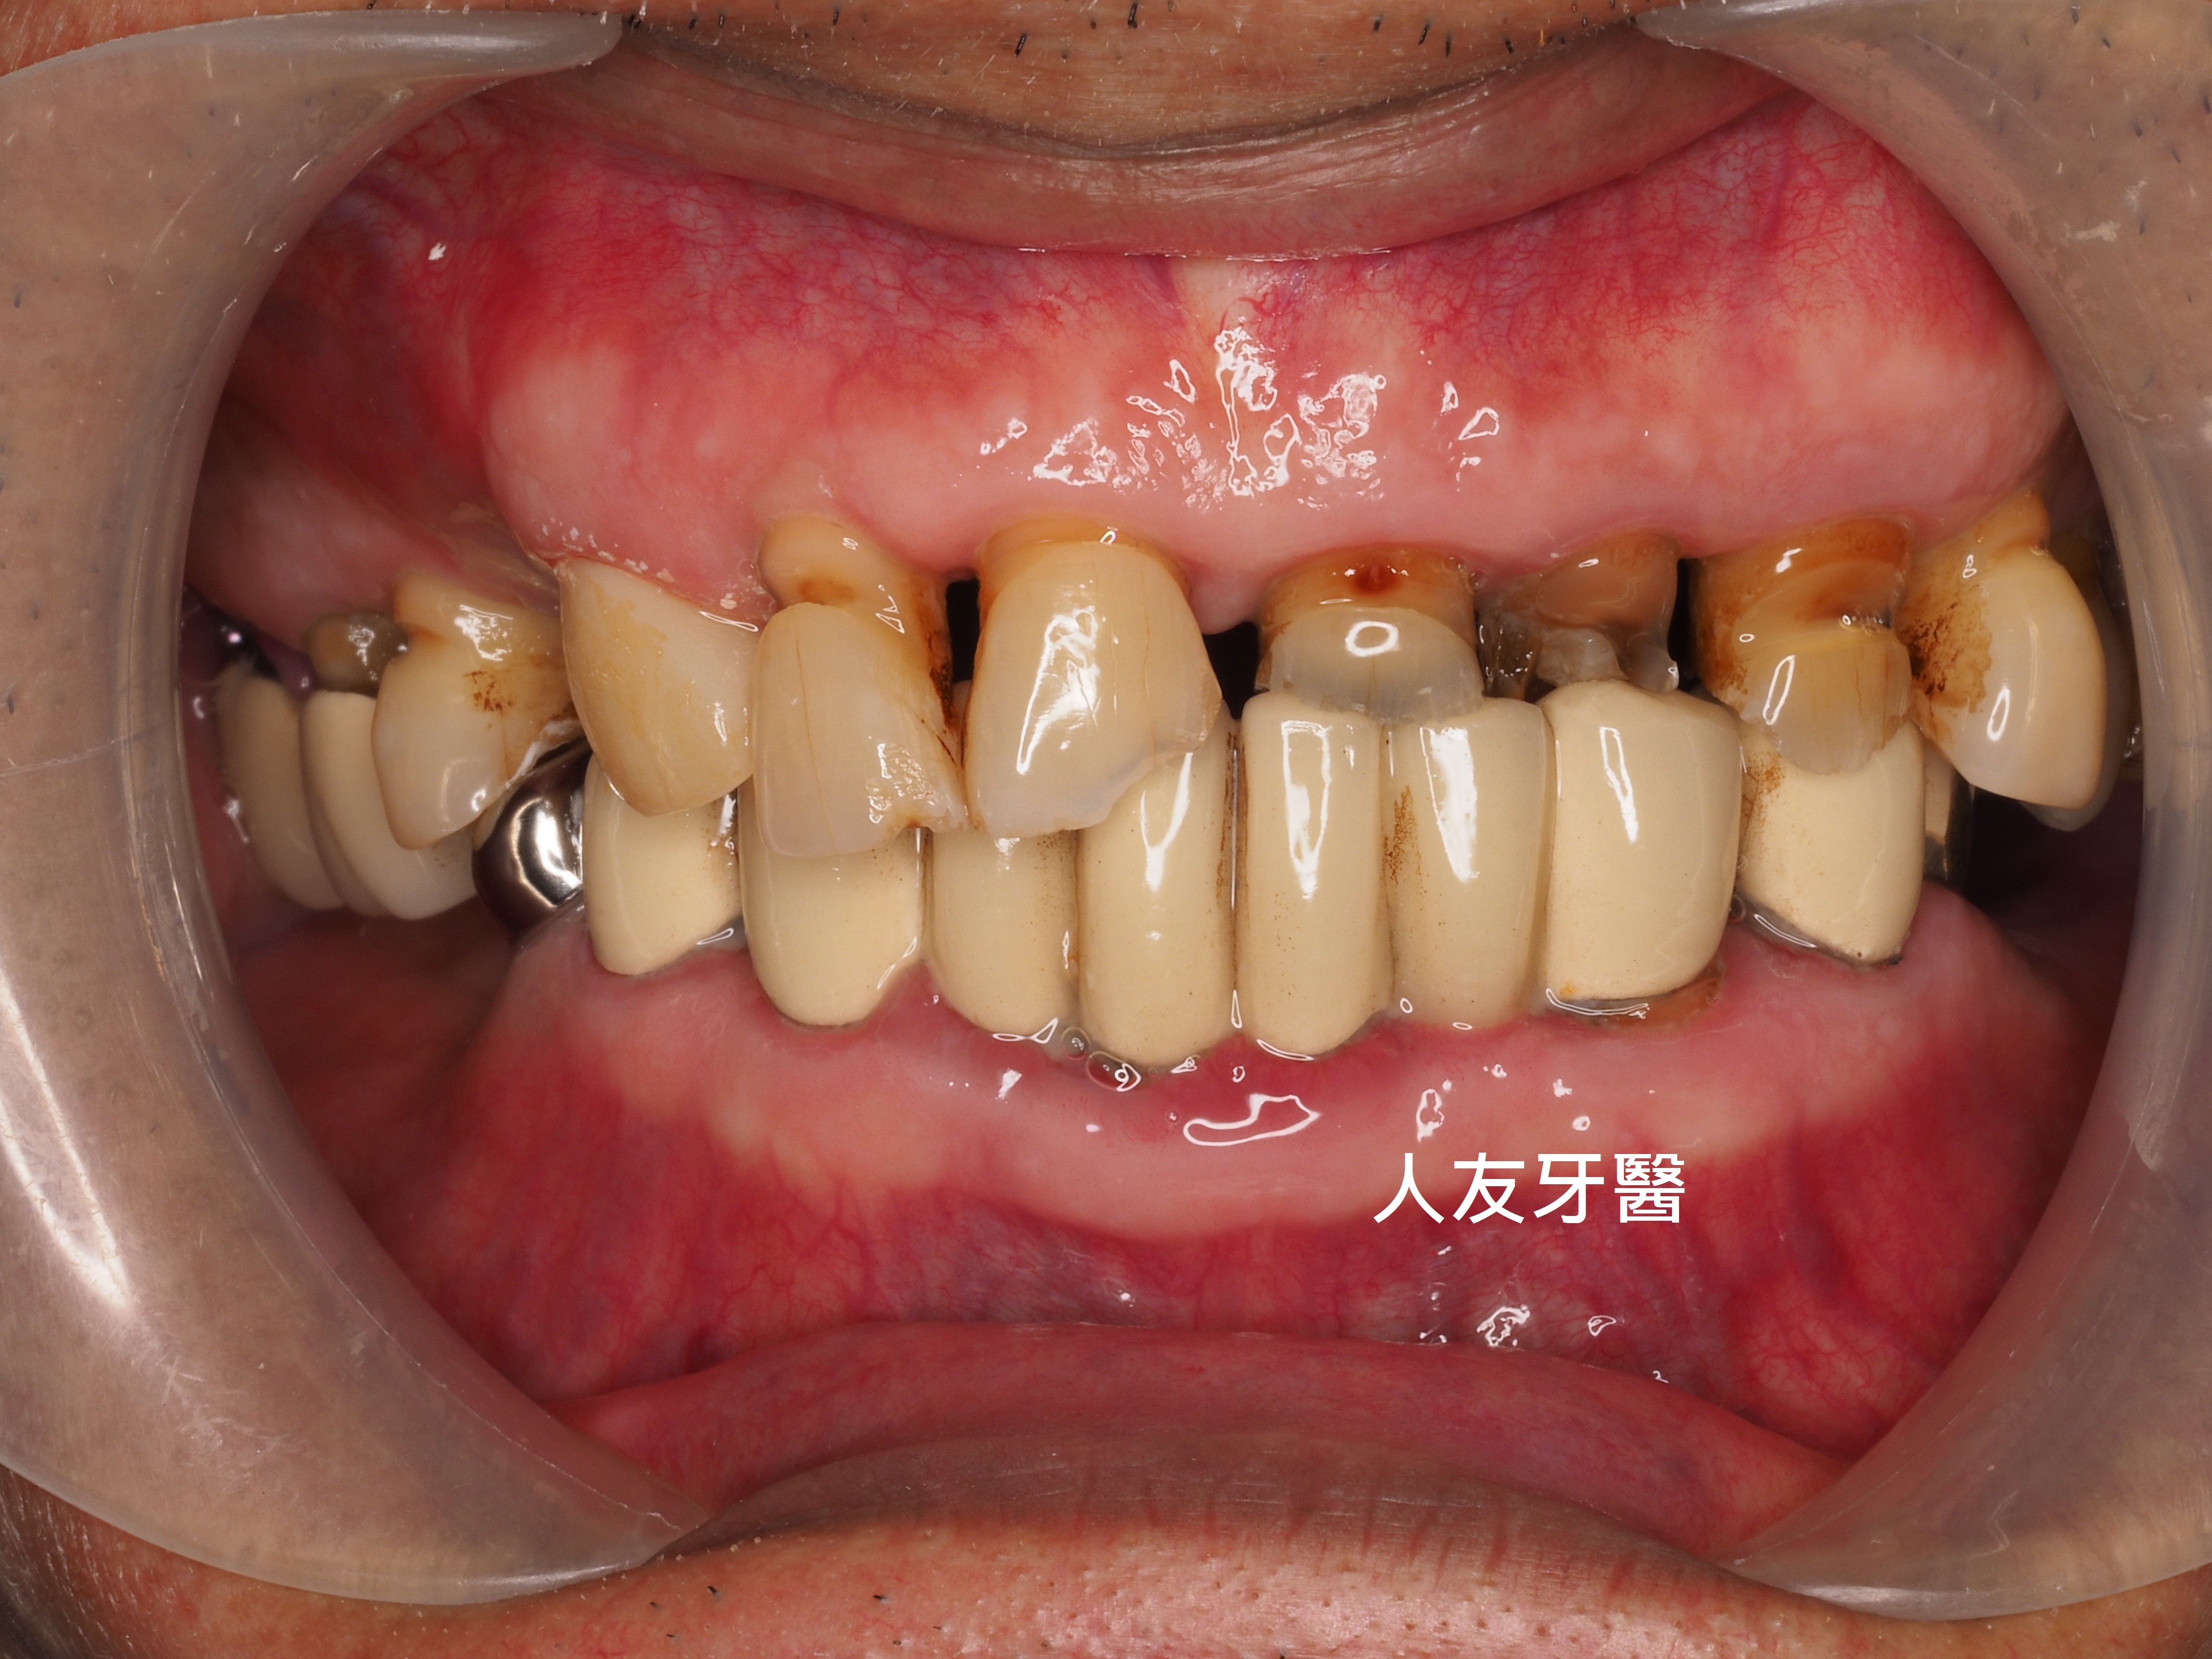

這位年輕女性患者的門牙和側門牙在別家治療半年,也有做四顆相連的牙橋,一直覺得很不舒服,笑起來不自然也不美觀,聽到鑽牙齒的聲音也很害怕。

下圖是別家做的牙橋

想詢問周醫師如何處理。醫師看了X-RAY發現右邊側門牙紅色圓圈的地方有病變,有可能留不住。左邊側門牙藍色箭頭牙齒有裂到肉,也可能留不住。經過討論後建議都拔除。